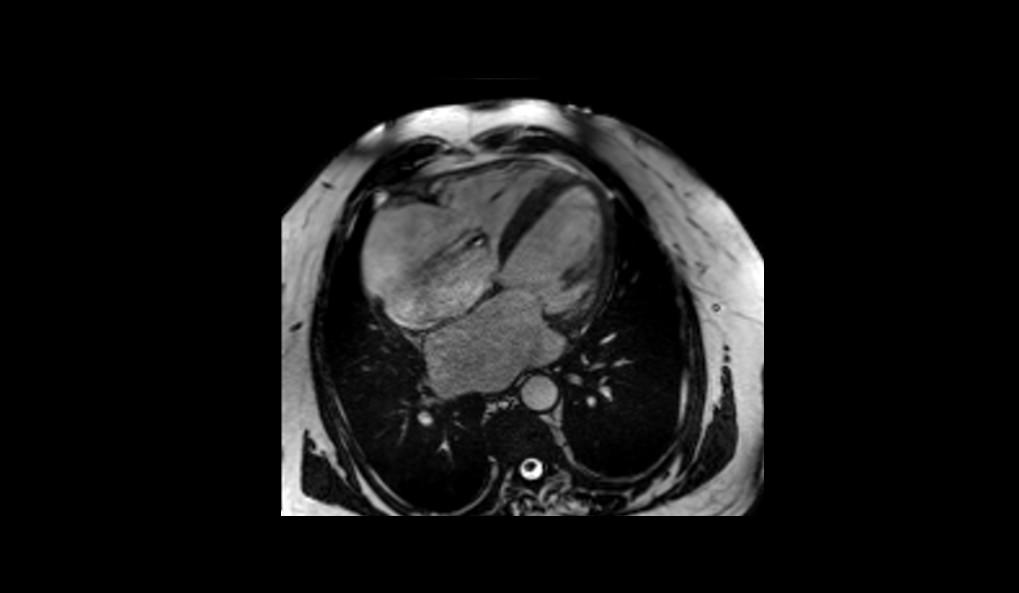

Paciente masculino, 76 años, en investigación de insuficiencia cardíaca clase funcional NYHA II. Se realizó ecocardiograma transtorácico evidenciando dilataciones biatrial y biventricular, disfunción diastólica grado III del VI, FEVI 37% y PSAP 60mmHg. Fue remitido para Resonancia Magnética cardíaca (RMC) para una mejor definición diagnóstica.

El examen de RMC se realizó en el equipo MAGNETOM Altea 1.5T. Se realizaron secuencias de CINE PSIF, FSE black-blood T1 y T2, phase-contrast, mapeo miocárdico (MyoMaps) T1/T2/T2* y LGE TRUFI high-resolution después de la inyección de contraste (DOTA-Gd 0,5M 0,2mmol/kg).

La RMC evidenció dilatación biatrial importante (AD=170ml/m2 y AE=120ml/m2), dilatación biventricular discreta (VDFVD=115ml/m2 y VDFVE=103ml/m2), FEVD 49%, FEVI 45%, rectificación del septo interventricular, insuficiencia tricúspide moderada, derrame pericárdico discreto, realce tardío heterogéneo en VI de patrones mesocárdico y subendocárdico en segmentos anteriores, anteroseptales, inferoseptales, inferiores y anterolaterales con distribución predominante medio-basal y realce tardío biatrial estadio UTAH IV. El MyoMaps en septo interventricular reveló elevaciones de tiempos T1 nativo (1070ms), T2 (58ms) y del volumen extracelular (33%) con T2* normal (28ms).

Los hallazgos de la RMC son compatibles con el diagnóstico de amiloidosis cardíaca. El patrón de cardiomiopatía dilatada con realce tardío (fibrosis) multisegmentar en VI, evitando segmentos apicales, elevaciones de T1 y VEC y fibrosis biatrial son hallazgos típicos de amiloidosis, especialmente en el subtipo ATTR. La Resonancia Magnética del Corazón, a través de su evaluación multiparamétrica, permite una diferenciación etiológica precisa de las cardiomiopatías, siendo indicada por las mejores guías como examen diagnóstico de primera línea en la investigación de insuficiencia cardíaca.